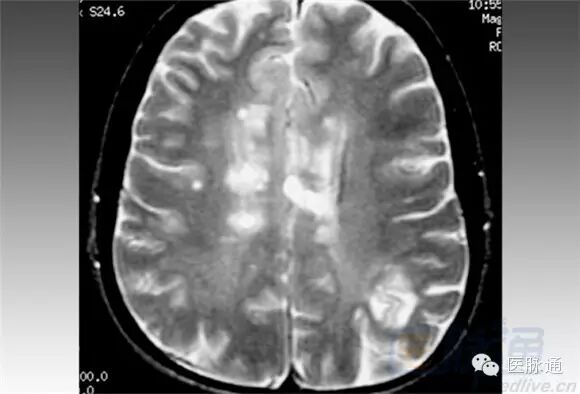

MRI对于评估复发型MS疾病进展是特别有效的。MRI所示为RRMS患者,前面的一张为同一患者3个月以后所做。病变的大小显著减小。